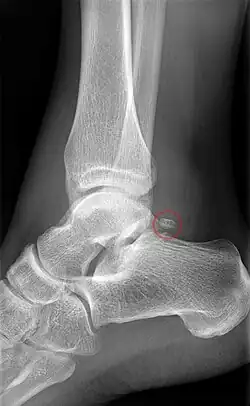

Os trigonum on X-ray

The body features several prominent articulate surfaces: On its superior side is the trochlea tali, which is semi-cylindrical,[6] and it is flanked by the articulate facets for the two malleoli.[3] The ankle mortise, the fork-like structure of the malleoli, holds these three articulate surfaces in a steady grip, which guarantees the stability of the ankle joint. However, because the trochlea is wider in front than at the back (approximately 5–6 mm) the stability in the joint vary with the position of the foot: with the foot dorsiflexed (toes pulled upward) the ligaments of the joint are kept stretched, which guarantees the stability of the joint; but with the foot plantarflexed (as when standing on the toes) the narrower width of the trochlea causes the stability to decrease.[7] Behind the trochlea is a posterior process with a medial and a lateral tubercle separated by a groove for the tendon of the flexor hallucis longus. Exceptionally, the lateral of these tubercles forms an independent bone called os trigonum or accessory talus; it may represent the tarsale proximale intermedium. On the bone's inferior side, three articular surfaces serve for the articulation with the calcaneus, and several variously developed articular surfaces exist for the articulation with ligaments.[3]

• The posterior surface is narrow, and traversed by a groove running obliquely downward and medialward, and transmitting the tendon of the Flexor hallucis longus. Lateral to the groove is a prominent tubercle, the posterior process, to which the posterior talofibular ligament is attached; this process is sometimes separated from the rest of the talus, and is then known as the os trigonum. Medial to the groove is a second smaller tubercle.